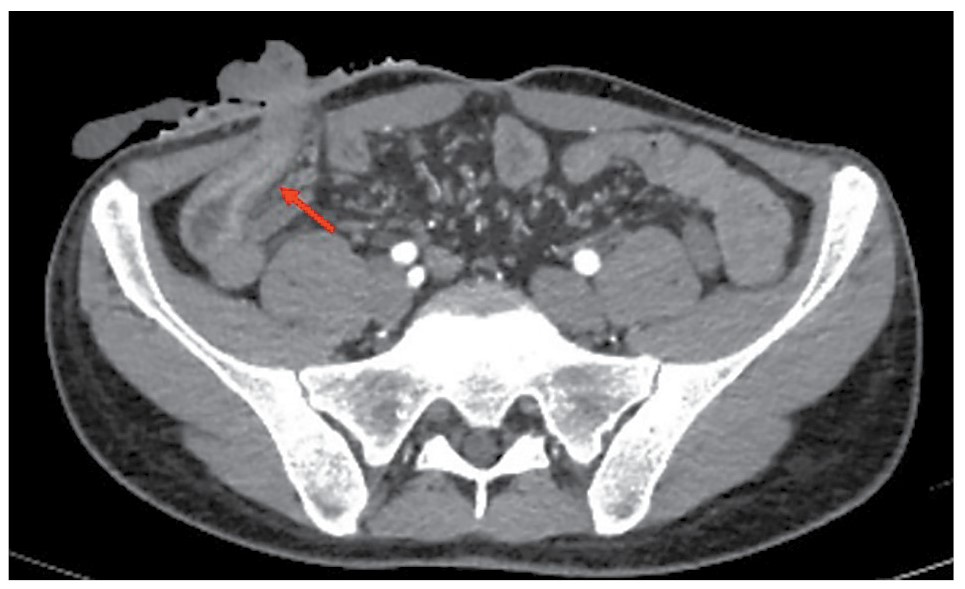

По данным КТ с энтерографией выявлены воспалительные изменения стенок илеостомы (рис. 3), ободочной кишки (рис. 4) и мезентериальная лимфаденопатия (рис. 5).

Рис. 4. КТ-энтерография. Картина воспалительных изменений стенок ободочной кишки.

Fig. 4. CT-enterography. Inflammatory changes in the colon.